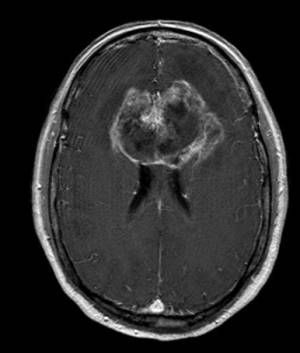

'Butterfly' glioblastoma is so named because of its tendency to cross midline over the corpus callosum to extend into the opposite hemisphere. It is a rare brain malignancy. It is a tumor with poor prognosis; the survival is few months after the diagnosis. Due to unfavorable position, surgical resection is not effective. Reference: https://www.nature.com/articles/s41598-021-93441-z#:~:text=Butterfly%20glioblastoma%20(bGBM)%20is%20a,risk%2Dto%2Dbenefit%20ratio. Image via: https://operativeneurosurgery.com/doku.php?id=butterfly_glioma